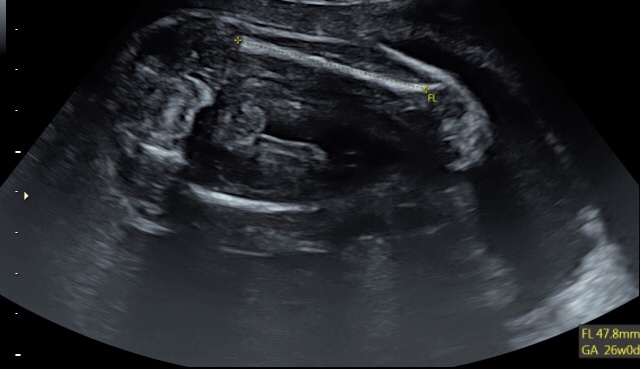

Hello can anyone let me know if they see anything in between my baby’s legs or not I have made a circle around what I think might be something there it’s not very visible tho and I’m not actually sure what it is

I don't feel I can get a good read on gender here because the rest of the baby isn't visible. Good luck!

Hello hun I don’t know if this is of any help but this is basically the full photo apart from the feet xxAttachment 42534

You have to zoom in a little on the photo to see what I’m talking about as it’s not completely visible well I don’t think it is xx

I need to see the top half of the baby with the head and stuff. I can't tell the "angle of the dangle" without that part of the baby. I see the nub, but I can't tell how it is lying in proportion to the body without the rest of the body to relate it to, if that makes sense.

Aw ok hun I’m 20 weeks so we didn’t get a completely full photo unfortunately thank you x